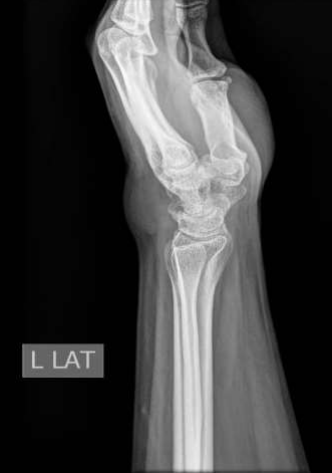

The patient had a solid hypoechoic lobulated mass lesion measuring 27x16mm on the dorsal aspect of his left wrist. The diagnosis was a giant cell tumor and soft tissue sarcoma, and fur-ther investigations were advised. X-rays showed a soft tissue shadow in the lateral view, but no bony abnormalities were noted. MRI scans revealed an irregular, intensely enhancing soft tissue mass at the wrist's dorsal aspect, interposed between the 4th and 5th extensor tendon compartments. The MRI findings were consistent with a benign soft tissue neoplasm.

Figures 1,2,3,4,5,6

Figure 4